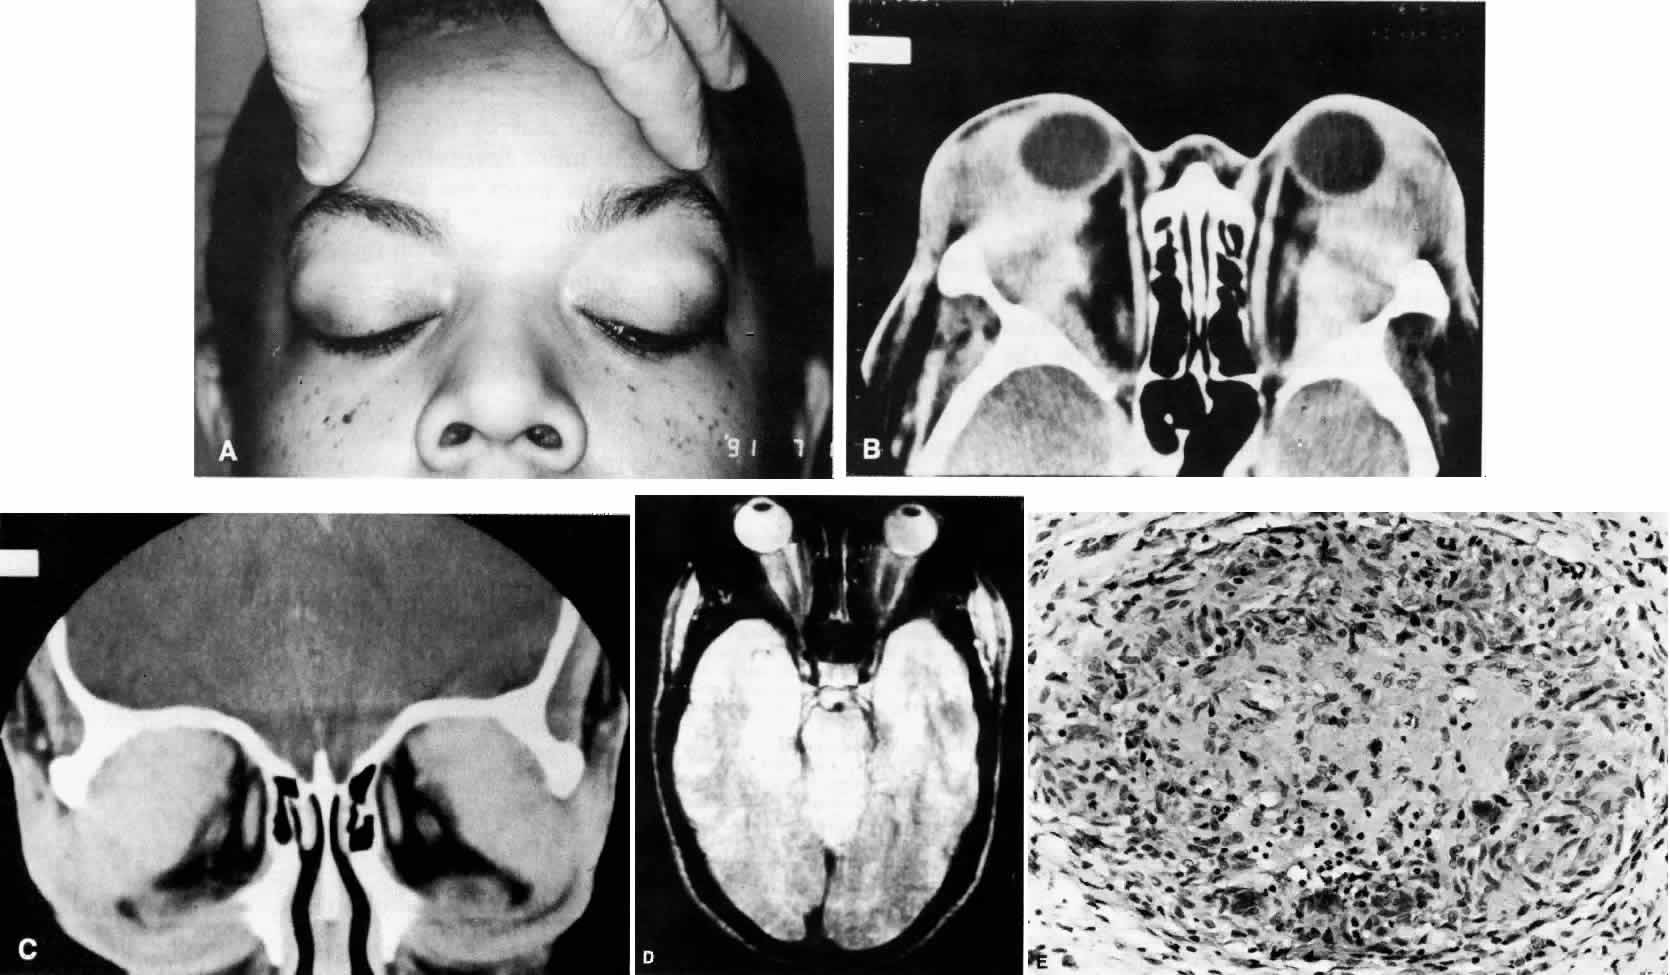

Fig. 11. A. This 31-year-old man has had Wegener's granulomatosis for 2 years. His disease process is stable on chronic corticosteroid therapy. He has no evidence of systemic disease. Note right-sided proptosis and hyperglobus. B. Profile of same patient demonstrating collapse of nasal bridge from bony destruction secondary to Wegener's granulomatosis. Note presence of swelling in lower eyelid. C. Axial CT image from the same patient demonstrating significant bilateral disease and bony destruction. Despite the extent of the orbital process on the right, the patient does not have diplopia. D. Coronal CT image showing destruction of medial orbital walls, vomer, and orbital septum. E. Pulmonary biopsy specimen from patient with orbital signs contains an almost obliterated vessel to right of center and scattered giant cells on left (H&E, ×160).